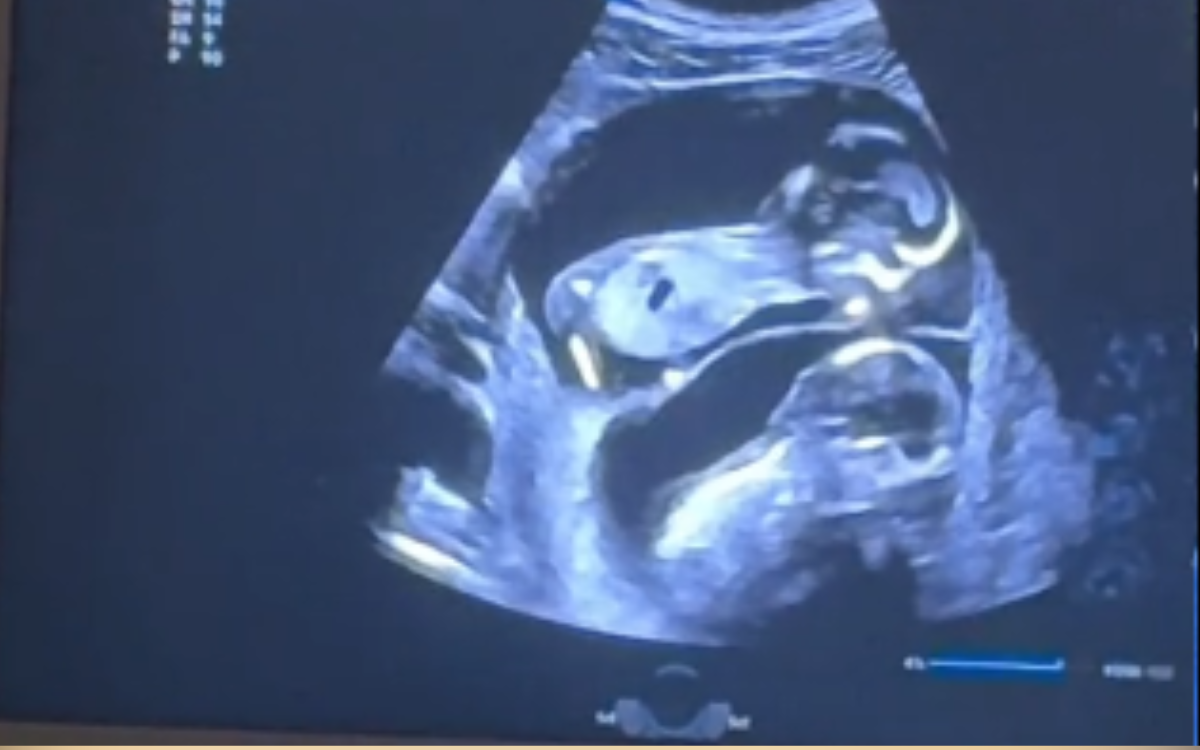

Hence then, the article about pregnant woman carrying twins has ultrasound shock at what it reveals was published today ( ) and is available on Newsweek ( Middle East ) The editorial team at PressBee has edited and verified it, and it may have been modified, fully republished, or quoted. You can read and follow the updates of this news or article from its original source.

Finally We wish PressBee provided you with enough information of ( Pregnant Woman Carrying Twins Has Ultrasound—Shock at What It Reveals )